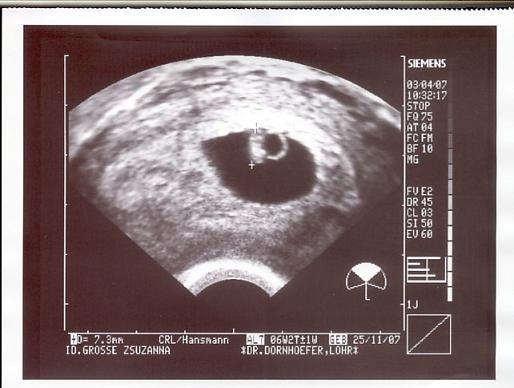

De jó, hogy Neked már ilyen kis korában is adtak képet. Nekem az elsőt a 20 heti uh-n adták, de azt is kérni kellett, de akkor már nem fért bele rendesen a poronty.